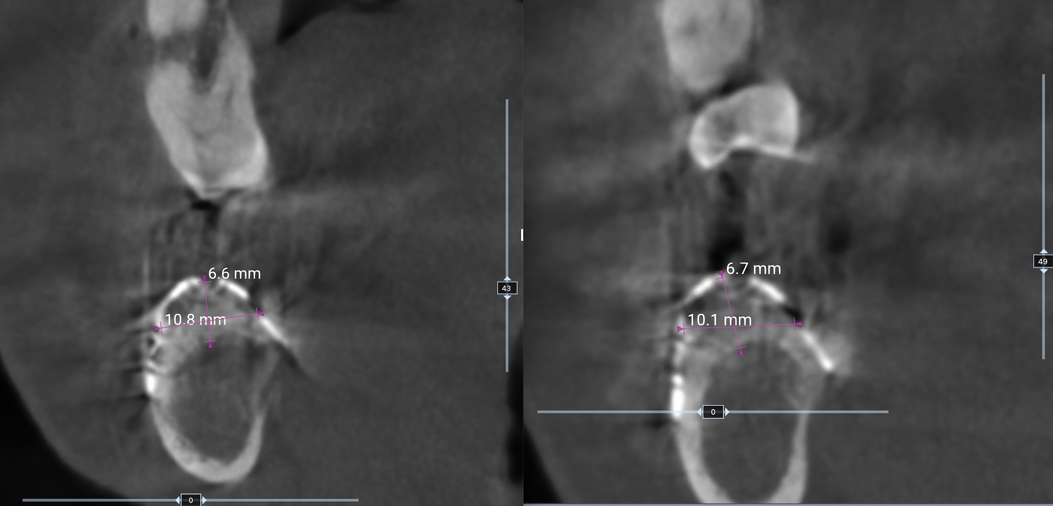

Fig 22. CBCT showing different gains of bone width before mesh removal, Patient 1.

Figure 22

Fig 23. CBCT showing different gains of bone width before mesh removal, Patient 2.

Figure 23

In each case, a CBCT was taken prior to mesh removal. Through the use of the measurement tool of the planning software, a calculation of the amount of bone gained was done. Patient 1 showed 4.1 mm vertical gain and a width of 8.7 mm (Figure 22). Patient 2 presented 6.7 mm vertical gain and a 10.8 mm width (Figure 23).